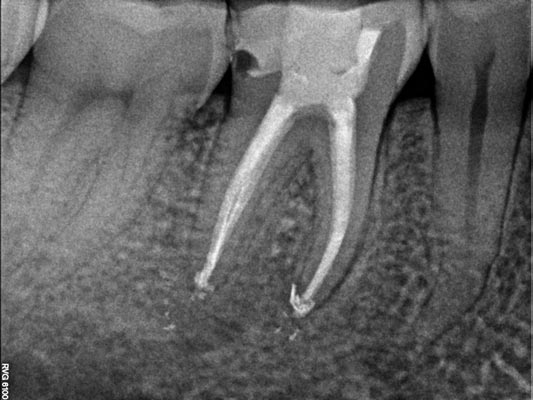

Tratamiento de Perforaciones

Las perforaciones son comunicaciones no deseadas entre el interior del diente y el tejido que lo rodea, que pueden producirse durante tratamientos dentales previos.

Ante la presencia de una perforación, es fundamental realizar un diagnóstico preciso y una valoración cuidadosa antes de iniciar cualquier tratamiento, ya que el tipo, la localización y el tamaño de la perforación influyen directamente en el abordaje y el pronóstico.

En estos casos, el CBCT resulta una herramienta especialmente útil, ya que permite estudiar la perforación en tres dimensiones y planificar el tratamiento de forma precisa y segura.

Imágenes:

Corte Axial de CBCT donde observamos material de relleno fuera del espacio del conducto radicular en el diente 2.2

Radiografías periapicales inicial y final con la resolución del caso

Imagen de la perforación y el conducto antes y después de la obturación.